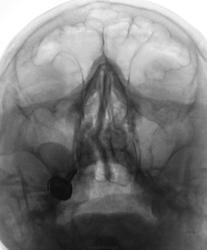

Пол пациента: Женский пол Тип патологии: Другое Область исследования: Челюстно-лицевая область и шея Методы исследования: Rg Пациент направлен отоларингологом на рентгенографии ППН. https://radiomed.ru/sites/default/files/styles/case_slider_image/public/user/12/2.pa130017.jpg?itok=v1ahIvCO https://radiomed.ru/sites/default/files/styles/case_slider_image/public/user/12/3.pa130018.jpg?itok=g_2UjqAl https://radiomed.ru/sites/default/files/styles/case_slider_image/public/user/12/4.pa130019a.jpg?itok=7_1J-Lyl ID:16132 Чт, 13/10/2011 - 20:10 #1 ДокRg Не на сайте Был на сайте: 12 лет 3 месяцев назад Зарегистрирован: 30.03.2011 - 20:05 Публикации: 105 Доброго времени суток уважаемые пользователи и гости сайта, моё мнение - одонтогенная киста правой в/ челюстной пазухи. Чт, 13/10/2011 - 20:16 #2 ДокRg Не на сайте Был на сайте: 12 лет 3 месяцев назад Зарегистрирован: 30.03.2011 - 20:05 Публикации: 105 и еще искривление носовой перегородки. Пт, 14/10/2011 - 18:48 #3 stovbav Не на сайте Был на сайте: 2 года 2 месяцев назад Зарегистрирован: 20.12.2009 - 17:28 Публикации: 7066 Согласен с коллегой...да и вспомнились высказывания на предмет не писать об искривлении перегородки...и как вот в ТАКОМ случае не написать? Болезни ног: виды, симптомы, причины, профилактика и лечение Пт, 14/10/2011 - 19:28 #4 Makcimalist Не на сайте Был на сайте: 11 лет 8 месяцев назад Зарегистрирован: 08.05.2010 - 14:28 Публикации: 1994 stovbav wrote: Согласен с коллегой...да и вспомнились высказывания на предмет не писать об искривлении перегородки...и как вот в ТАКОМ случае не написать? - Согласен! Считаю, нужно описывать такие отклонения от нормы! -------------- "Просто, по видимости, не видеть логики в очевидных вещах - это тоже одно из свойств некоторых умов, наряду с грустными думами о свойствах ума других." © Vega 08/10/2011 Пт, 14/10/2011 - 21:28 #5 Катенёв Валенти... Не на сайте Был на сайте: 7 лет 2 недели назад Зарегистрирован: 22.03.2008 - 22:15 Публикации: 54876 А, киста, прям - Венера Милосская!

Доброго времени суток уважаемые пользователи и гости сайта, моё мнение - одонтогенная киста правой в/ челюстной пазухи.

и еще искривление носовой перегородки.

Согласен с коллегой...да и вспомнились высказывания на предмет не писать об искривлении перегородки...и как вот в ТАКОМ случае не написать?